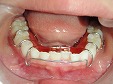

入れ歯治療

◆総入れ歯

当院の総入れ歯では、リンガライズド・オクルージョンという特別な噛み合わせで製作しております。この噛み合わせの特徴は、小さな力で食品を破砕することが可能となり、顎堤が吸収して食事中、入れ歯の安定が悪い方にお勧めです。

総入れ歯1

総入れ歯2

総入れ歯3